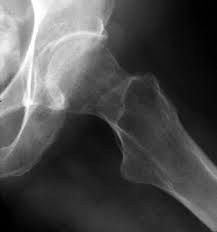

OssaL’osteoporosi può essere prevenuta con 20 minuti al giorno di esposizione ai raggi solari. Il suggerimento altamente qualificato proviene dalla Società Italiana dell’Osteoporosi, del Metabolismo Minerale e delle Malattie dello Scheletro (Siomms). L’esposizione al sole purché sia moderata, stimola la produzione di vitamina D. Non è un elemento di poco conto, basti solo considerare che in Italia i 70% della popolazione sofffre di ipovitaminosi D, carenza di calcio e conseguente fragilità ossea. A soffrirne maggiormente sono le donne.

In realtà i fattori che aumentano il rischio di osteoporosi possono essere contrastati efficacemente sia con l’esposizione settimanale al sole per 20 minuti al giorno, con braccia, viso e gambe scoperte e sia con la dieta che privilegi alimenti quali salmone affumicato, sgombro sotto sale., olio di fegato di merluzzo e anguilla. Insomma l’esposizione al sole per la vitamina D e la dieta lavorano sinergicamente per prevenire questo problema.